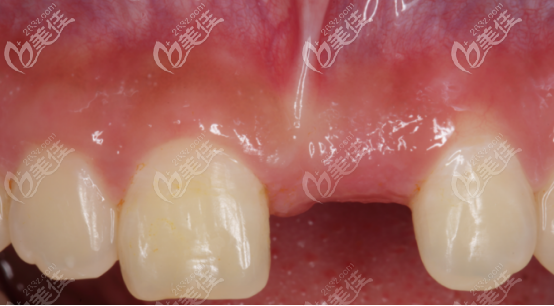

術前正面門牙照片,可以看出缺牙的位置骨量不足,而且中度凹陷。